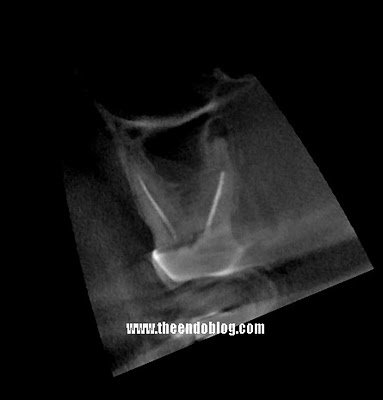

While the lesion on the palate of #2 is visible in the original radiograph, there is no doubt about it’s presence with the sagittal view above.

In this case the additional information about the palatal lesion on #3 changed the treatment recommendation and will thereby improve the prognosis. Lack of CBCT scan in this case would have led to wrong treatment recommendation.